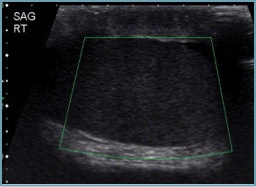

Normal testicle has normal echogenicity, normal color doppler flow within testicle: